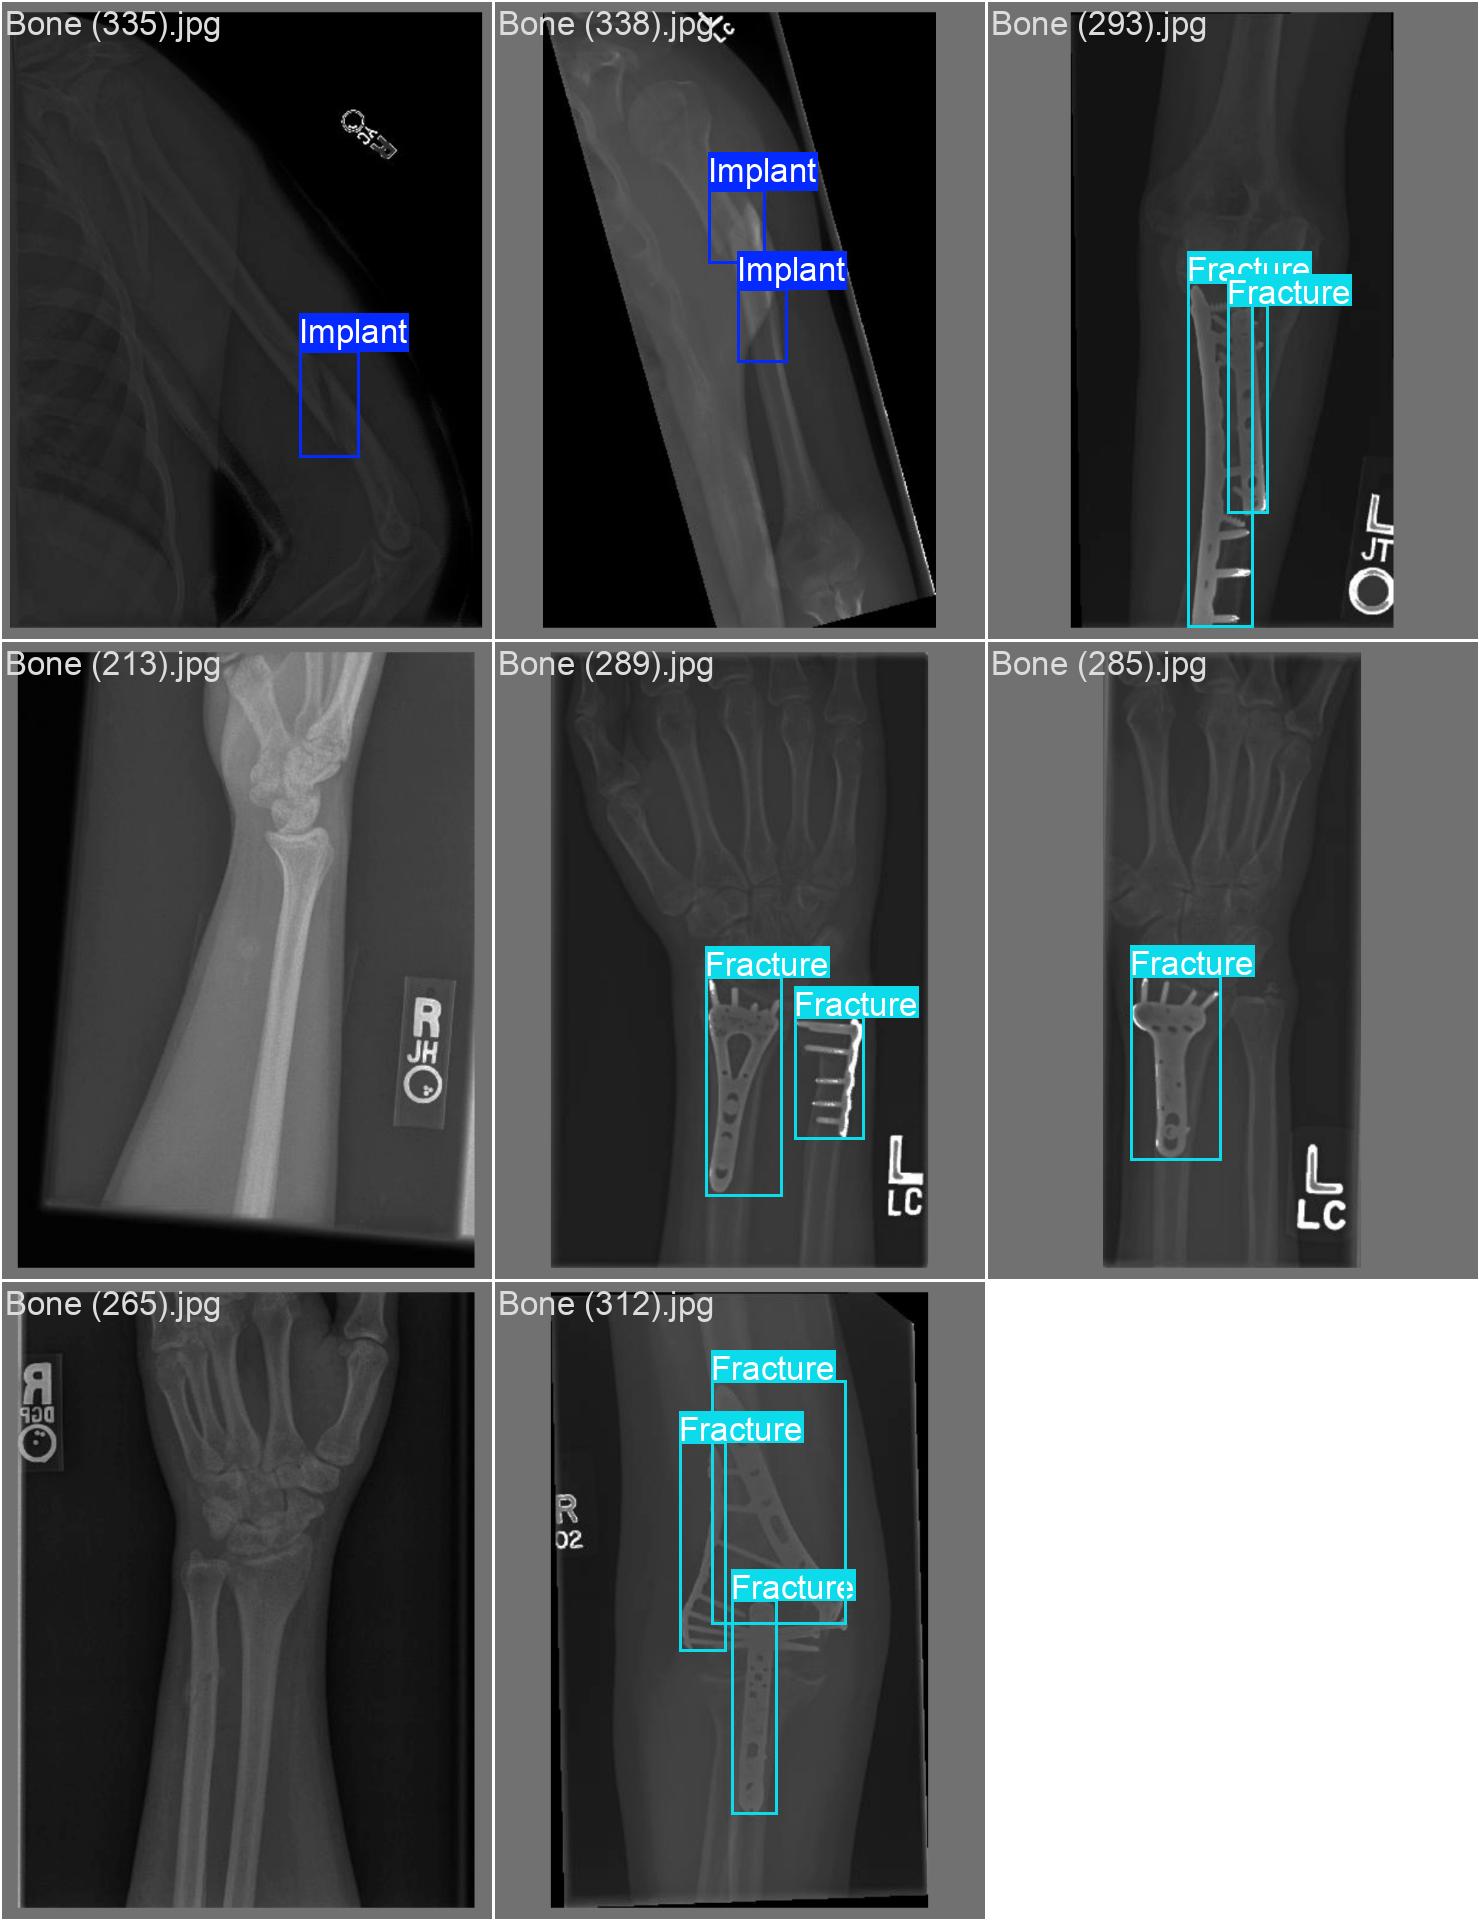

20251204_03 train

| model | yolov8s.pt | |

| imgsz | 800 | |

| batch | 16 | |

| epochs | 100 | 100까지 의미가 있다고 하니, 100까지 올려보자 |

| optimizer | auto |

20251204_03 predict

아 또 계정 바꾸면서 class 반대로 되어있는 파일로 넣었다

| conf | 0.3 | |

| iou | 0.5 | 줄여보기 |

아니 아까보다 더 안 좋아졌다.